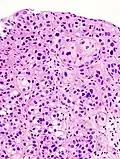

Histopathology of urothelial carcinoma of the urinary bladder, showing a nested pattern of invasion. Transurethral biopsy. H&E stain -

Histopathology of urothelial carcinoma of the urinary bladder. -